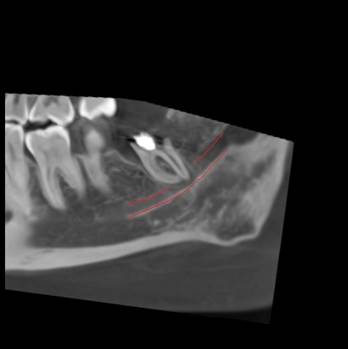

Перед любым лечением мы делаем КТ-снимок челюсти. Дальше в работу включается программа Diagnocat, которая превращает его в детализированную 3D-модель.

Так мы видим нервы, каналы, сложные изгибы челюсти, которые можно не заметить на обычном снимке. На экране можно буквально убрать нижнюю челюсть и посмотреть, как нерв проходит между корнями зуба или где он оказывается особенно близко к потенциально проблемному участку.

Для пациента такая 3D-картинка очень наглядна: вместо того чтобы разглядывать непонятные чёрные полоски на стандартном КТ, он видит полноценную визуализацию.

Если видим такую картину, например, сразу объясняем, что зуб находится в опасной близости к нерву и обычное удаление может быть рискованным.